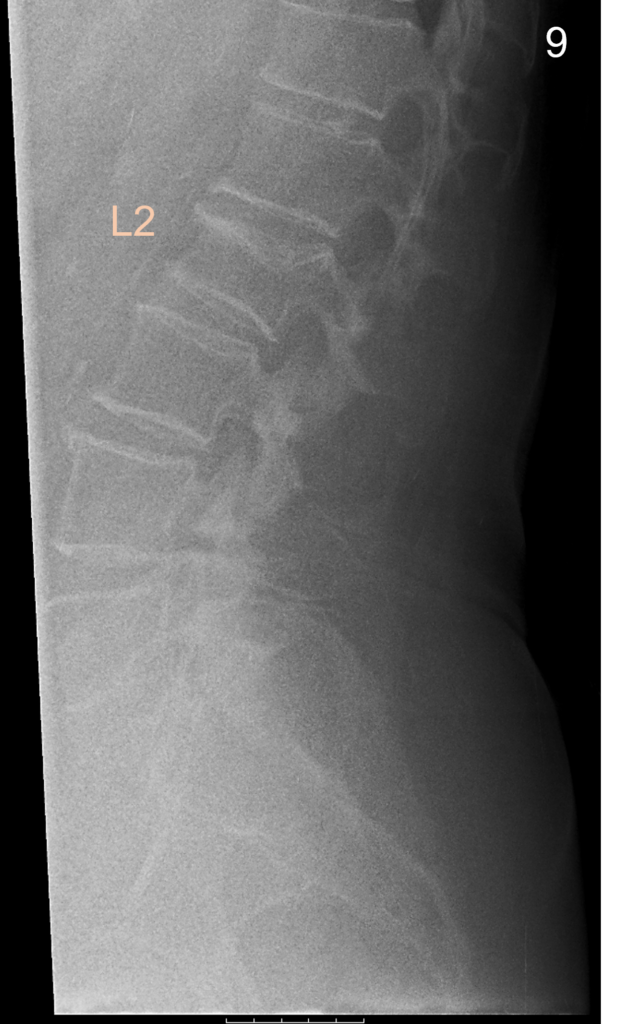

La classificazione di Genant

Il radiologo o l’operatore specializzato esamina le vertebre da T4 a L4 e assegna a ciascuna un punteggio di gravità basato sulla riduzione percentuale dell’altezza vertebrale rispetto all’altezza di riferimento (solitamente l’altezza posteriore della stessa vertebra o l’altezza di una vertebra adiacente sana).

| Grado di frattura | Riduzione % dell’altezza | Descrizione clinica |

|---|---|---|

| Grado 0 | <20% | Vertebra normale |

| Grado 1 (lieve) | 20−25% | Frattura lieve (spesso asintomatica) |

| Grado 2 (moderato) | 25−40% | Frattura moderata (impatto biomeccanico) |

| Grado 3 (grave) | >40% | Frattura severa o collasso totale |

La misurazione quantitativa computerizzata automatizza questo processo posizionando sei punti (reperi) su ogni corpo vertebrale, calcolando istantaneamente i rapporti tra le altezze anteriore, centrale e posteriore.

Sebbene la misurazione automatica sia rapida, la supervisione del radiologo è indispensabile per confermare la natura osteoporotica della deformità e non confonderla con varianti anatomiche o processi degenerativi.